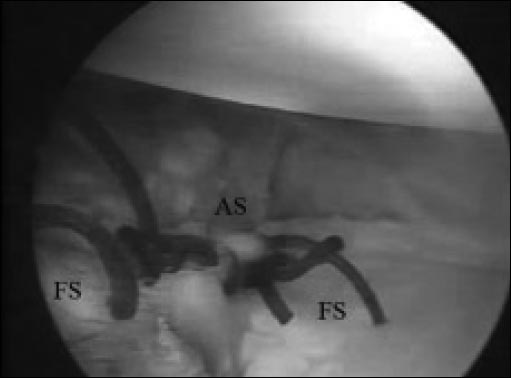

Figura 2: AS: (anchor suture) sutura de anclaje Fijación del anclaje en la posición de la hora 5, con las suturas libres fuera de la cánula.